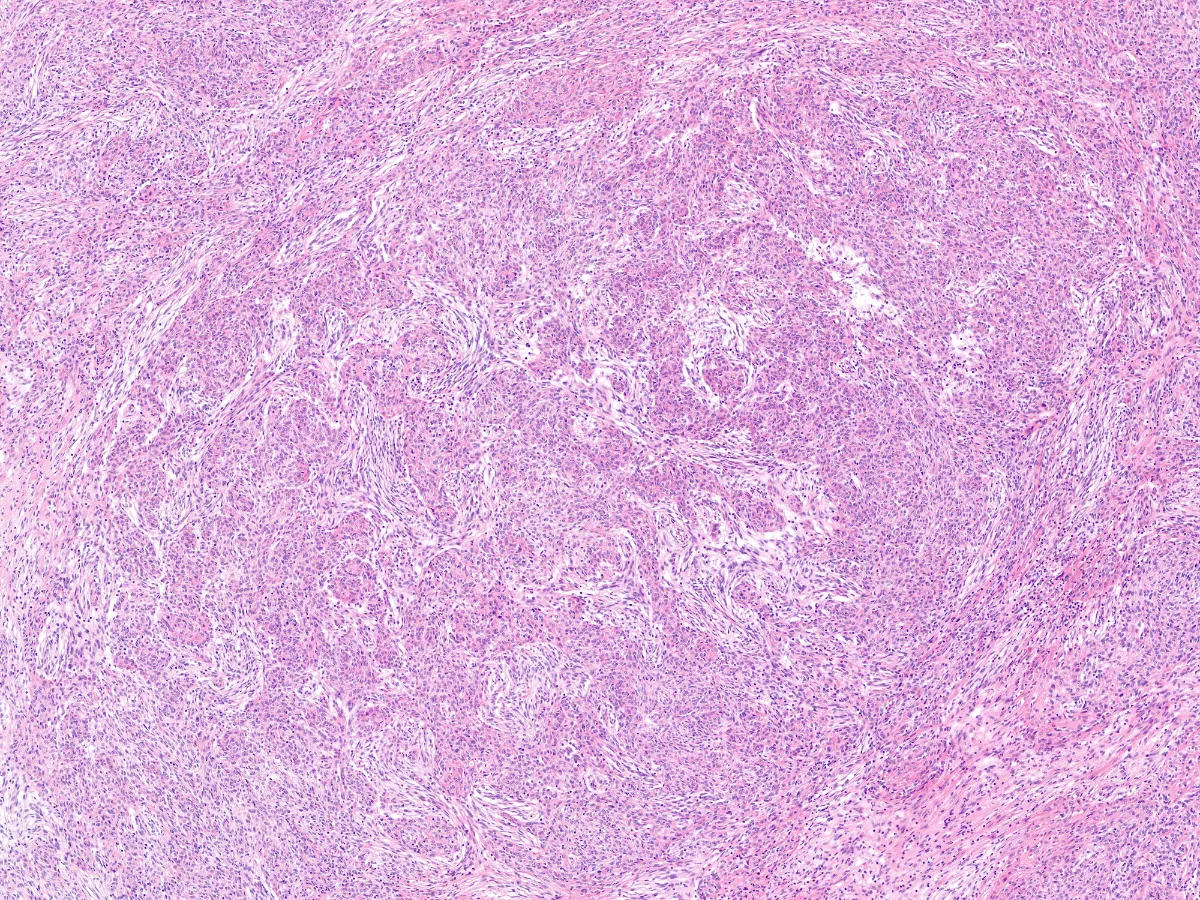

2. HE 10x

Diagnóstico: Timoma metaplásico

- Se trata de un tumor bifásico de origen tímico compuesto por islas de células epiteliales y células fusiformes de bajo grado citológico, con áreas de transición de gradual a abrupta entre ambos componentes.

- Con técnicas de inmunohistoquímica las células epiteliales expresan CK, p63/p40 y EMA, así como negatividad para Vimentina. Las áreas fusocelulares, por el contrario, expresan Vimentina, positividad focal o negatividad para Citoqueratinas y EMA y negatividad para p63 y p40. Ambos componentes son negativos para CD5, CD20, CD34 y CD117 (c-kit). El índice de proliferación Ki67 es bajo en ambos componentes (<5%).